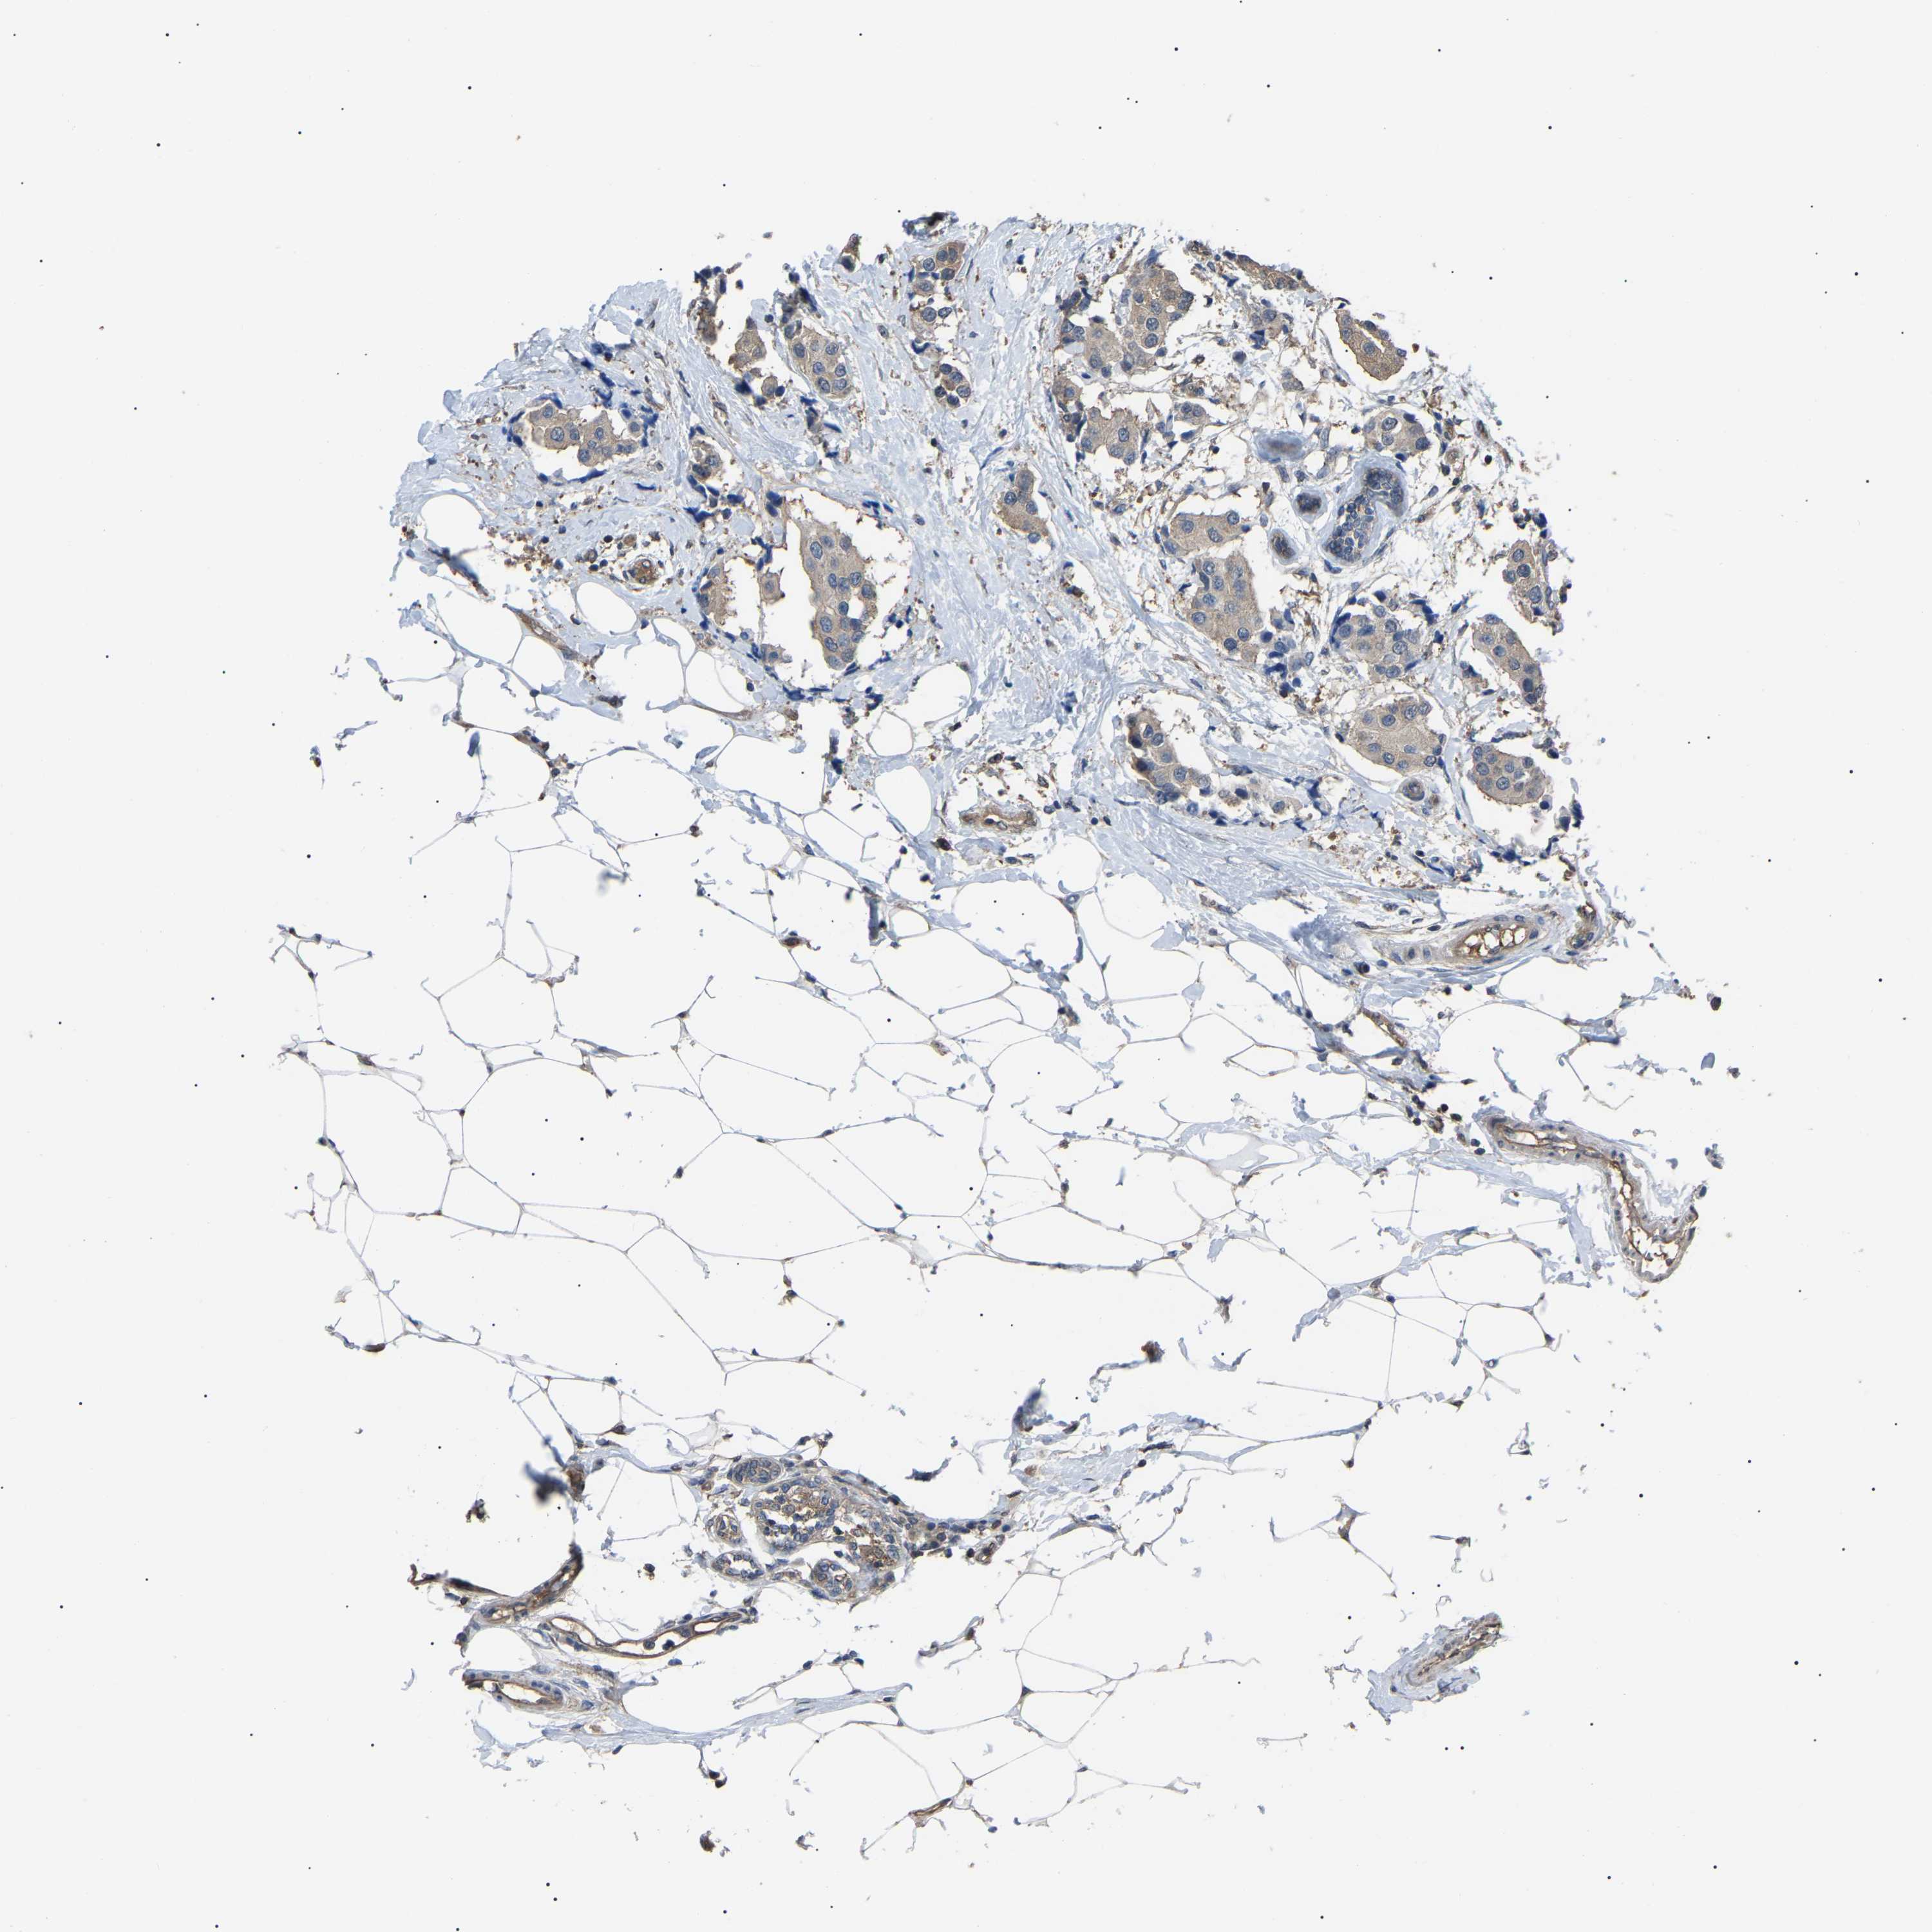

CANCER BREAST CANCER Show tissue menu

BRCA TCGA BRCA VALIDATION PROTEIN EXPRESSION

Breast cancer

Human cancer